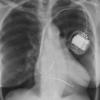

normal vessels

Date: 02/25/2013

Views: 3288